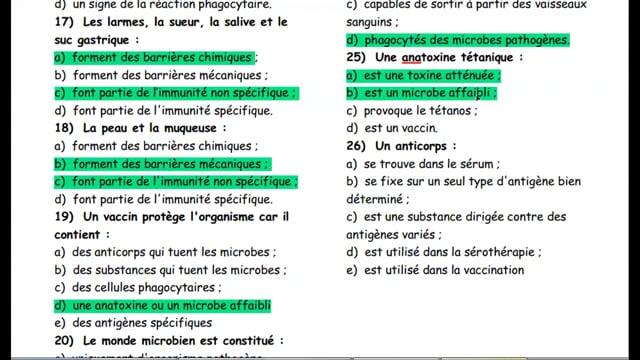

Sciences SVT